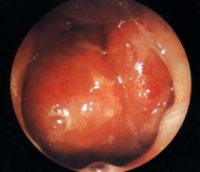

Bki7y.jpg

(一)前鼻孔镜检查 :鼻粘膜收敛后经前鼻孔镜可窥到后鼻孔和鼻咽部能发现侵入或邻近鼻孔的癌肿。

(二)间接鼻咽镜检查 :方法简便实用,应依次检查鼻咽的各壁,注意鼻咽顶后壁及两侧咽隐窝要两侧相应部位对照观察,凡两侧不对称的粘膜下隆起或孤立性结节更应引起注意。

(三)纤维鼻咽镜检查 :进行纤维鼻咽镜检查,可先用1%麻黄素溶液收敛鼻腔粘膜、扩张鼻道,再用1%地卡因溶液表面麻醉鼻道,然后将纤维镜从鼻腔插入,一面观察一面向前推进直到鼻咽腔。本法简便,镜子固定好,但后鼻孔和顶前壁观察不满意。